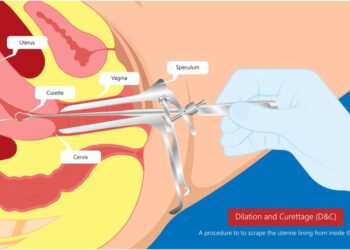

All Laparoscopic Surgeries

Laparoscopy is one of the diagnostic procedures or a surgical treatments which is performed for examining the organs inside the abdomen. It is also termed as diagnostic laparoscopy. In this procedure, an instrument called a laparoscope is used that has a light and camera on it.